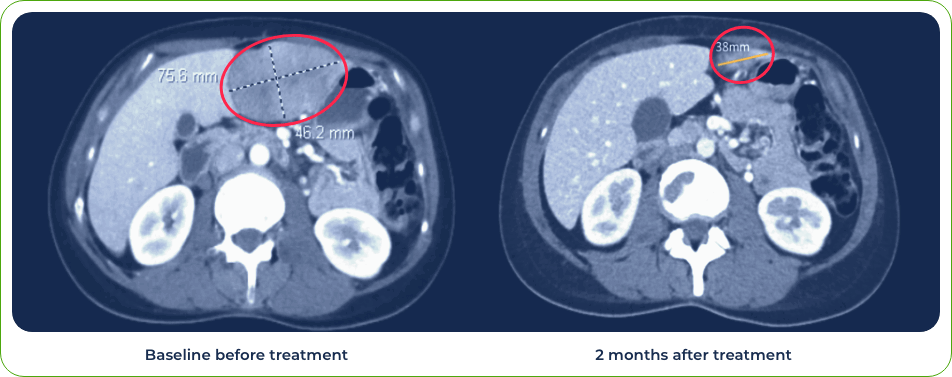

Diagnosis:

Stage IV metastatic melanoma

Single dose induced regression of large metastatic lesion in the liver